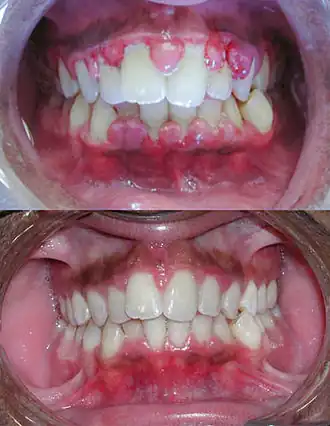

On observe une augmentation de volume importante (parfois on ne voit même plus les dents). La gencive est très fibreuse ; la texture et la teinte restent normales (car on ne voit pas la partie enflammée).

L'étiologie est la prolifération des fibroblastes. Elle est parfois d'origine idiopathique, mais le plus souvent elle est favorisée par certains médicaments : certains antiépileptiques, la ciclosporine, la nifédipine et certains bêta-bloquants).